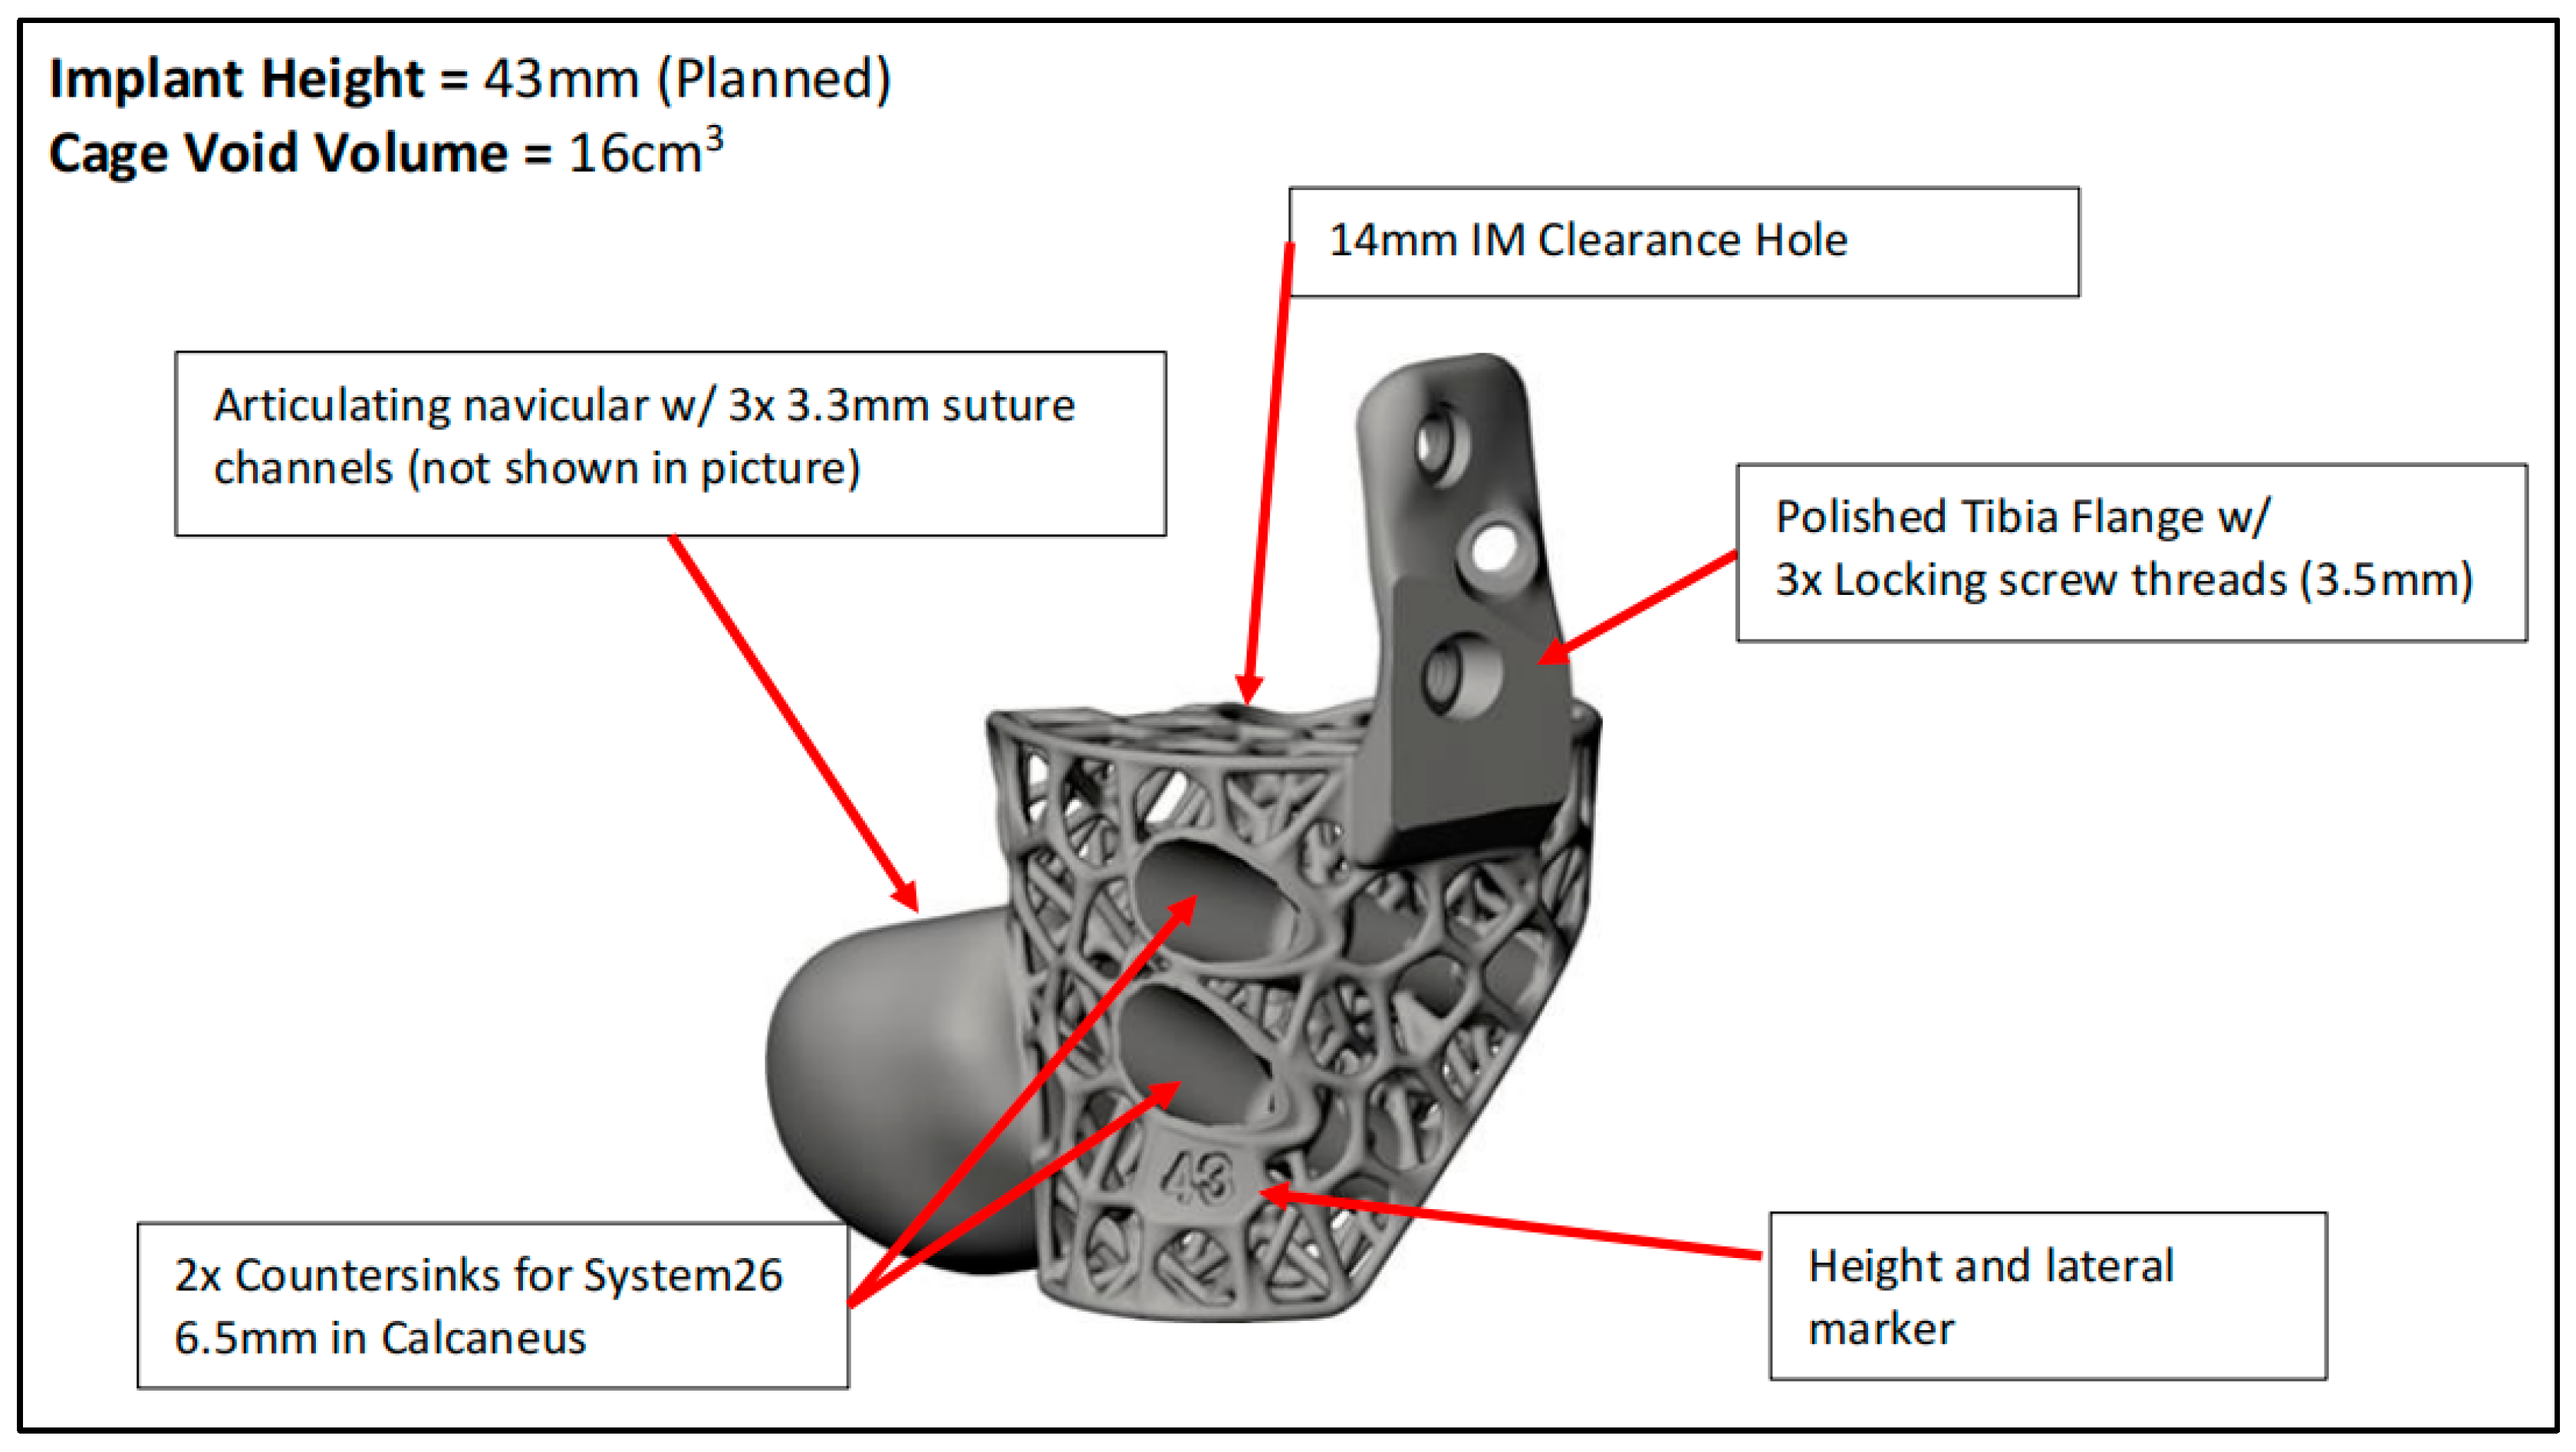

2.1. Preoperative Planning

2.2. Surgical Technique